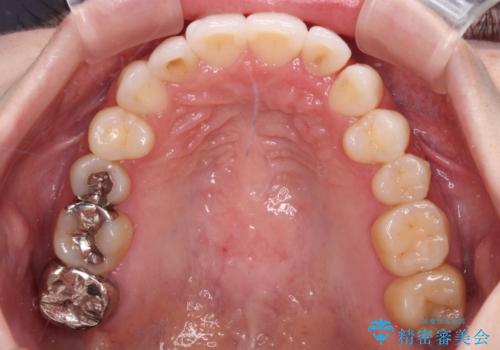

- 前歯のデコボコや八重歯の様になっていることを気にして来院された患者様です。

犬歯捻れて前方に飛び出しており、下顎前歯もそれに沿うようにデコボコとなっていました。

IPR(歯と歯の間を削る処置)によりスペースを獲得して上下顎前歯のデコボコを改善し、前歯が前方に突出しないように設定した上で、インビザラインにて矯正治療を行うこととしました。